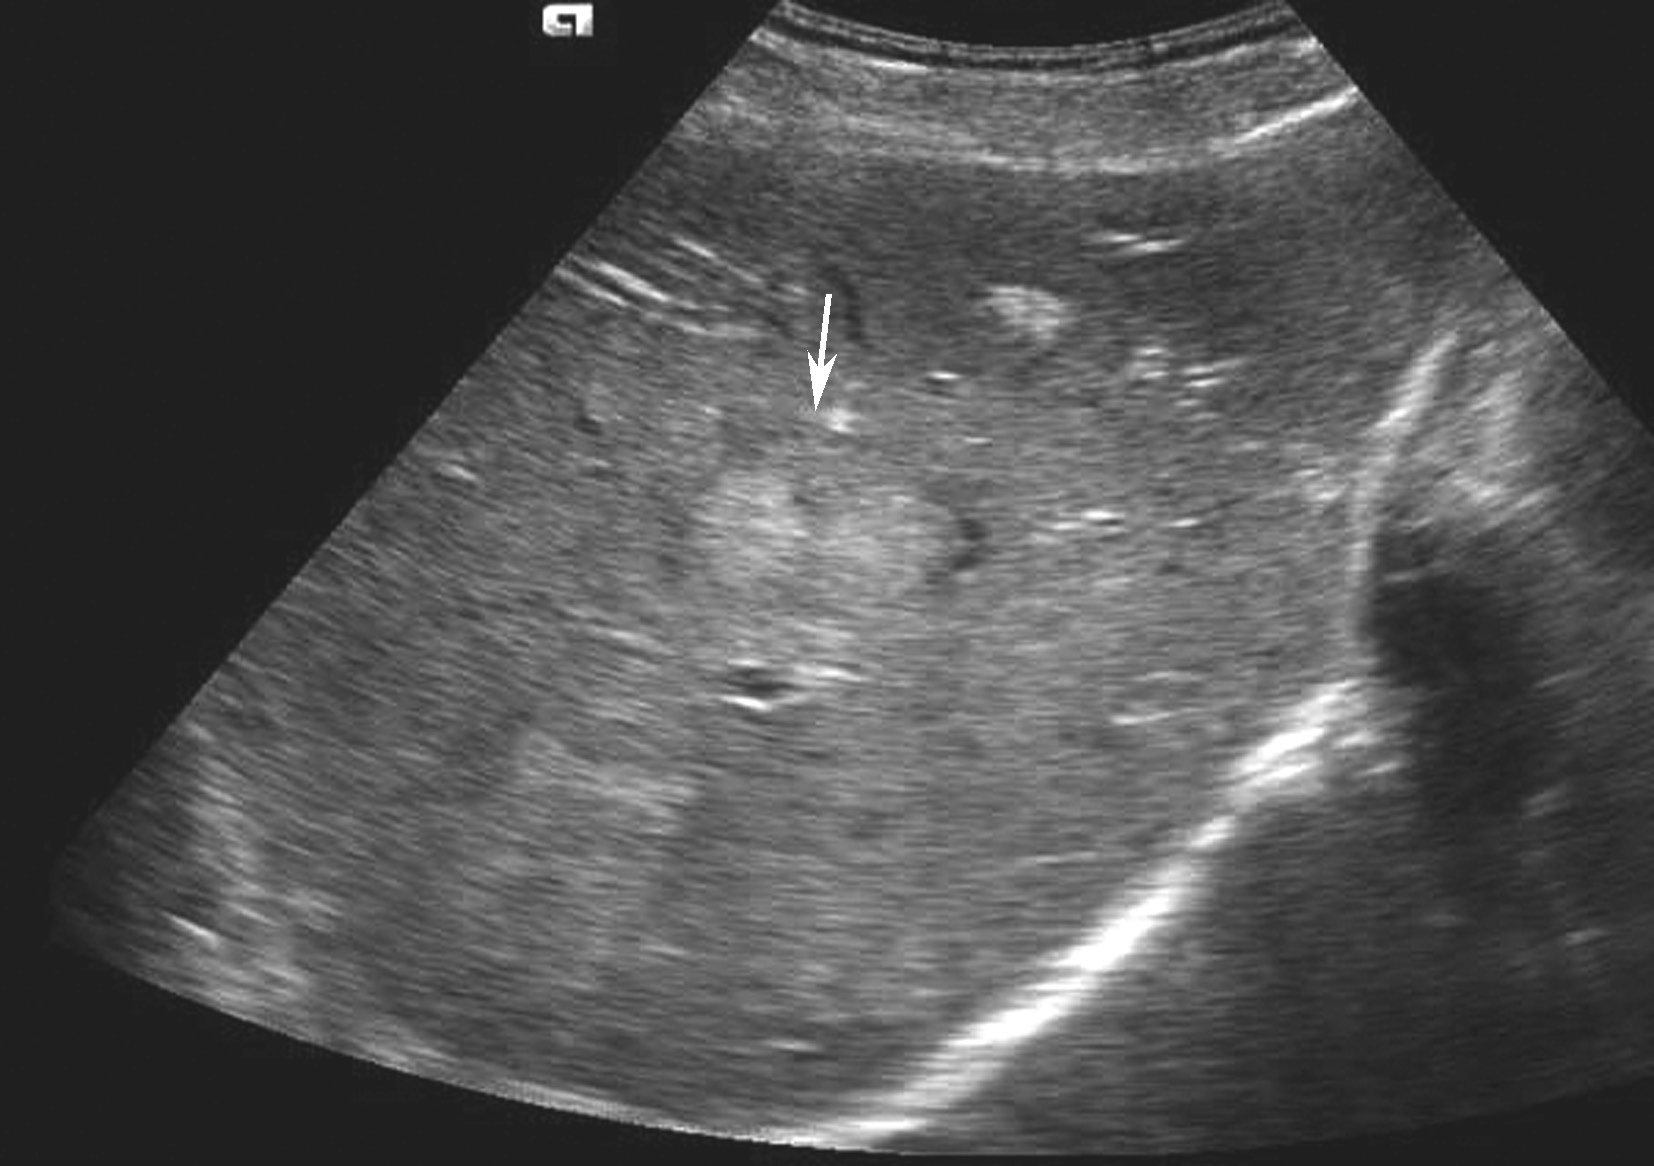

是肝脏最常见原发性恶性肿瘤,绝大部分病例与乙、丙型肝炎和肝硬化有关,占肝恶性肿瘤的80%~90%,男性多见,与乙肝和黄曲霉素相关,分为块状型、结节型、弥漫型及小癌型。在肝硬化的患者中,小的局灶性病变几乎代表着早期肝细胞癌或增生结节。小肝癌二维灰阶图像如图5-21-17所示。

图5-21-17 小肝癌二维灰阶图像

1)灰阶超声:

C.肿块内部回声类型:①低回声型:肿瘤回声低于周围肝组织。常呈圆形或类圆形,边界较清,具有细包膜,病变较小,常仅1~2cm,内部回声欠均匀,后方回声略增强。②高回声型:肿瘤回声高于周围肝组织,内部回声多不均匀。外形可为圆形或不规则分叶状,部分有假包膜形成者界限清晰。此型癌肿多较大。③等回声型:此型回声肝癌与周围肝组织密度相似,仅有微弱分界,易漏诊。对可疑病灶可使用高频超声进行检查,增加病灶检出率。④混合回声型:此型多见于体积较大的肝癌,癌肿内可同时出现多种类型回声,多种回声交织混合成为一体;如癌肿内出现不规则无回声区,其内可见点状或斑状高回声,多为癌肿内出血、坏死或液化。⑤弥漫型:癌肿数目众多,呈弥漫散布于整个或局部肝脏,直径多在1cm左右。内部回声高低不均匀。该类癌肿常伴有肝硬化,在声像图上有时很难与肝硬化结节鉴别,但弥漫型肝癌易伴发门静脉及肝静脉内癌栓和肝脏深部组织回声衰减。